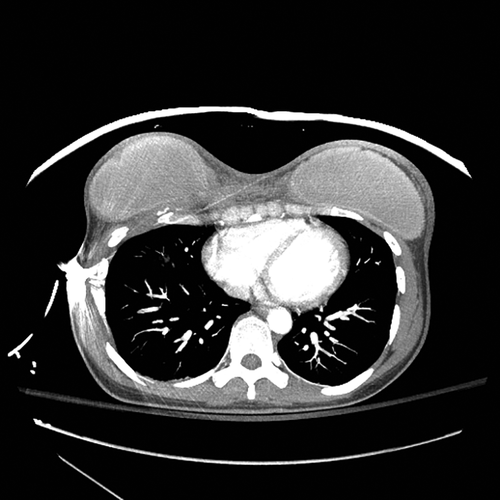

Figure 9. Аксиальная компьютерная томография (КТ), показывающая конечное положение пули в покое с артефактом и переломом ребра на правой стороне грудной клетки.